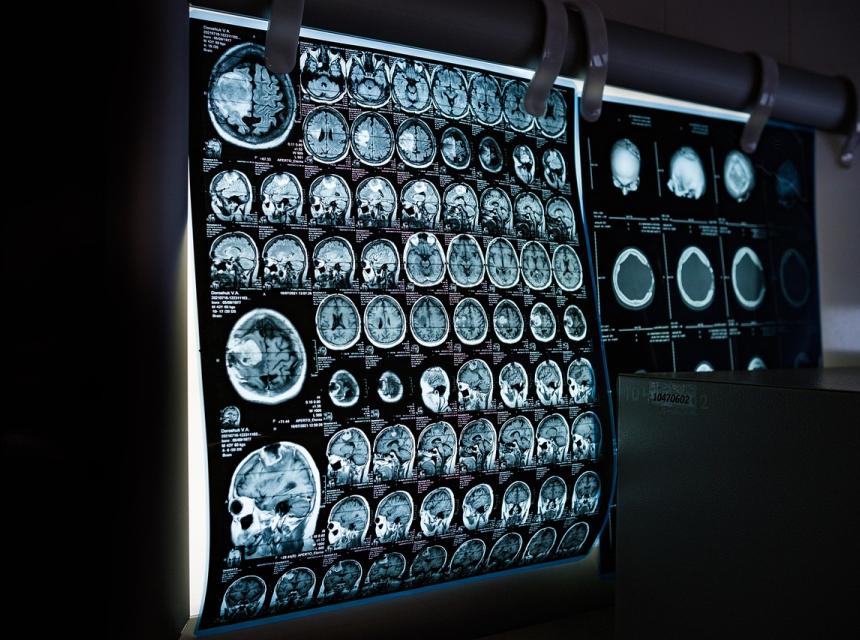

Přišla jsem k vám se spoustou potíží, které žádný lékař nedokázal vyřešit, a z poslední návštěvy z neurologické ambulance jsem odcházela se zprávou, že je třeba udělat lumbální punkci k vyloučení roztroušené sklerózy. Magnetická rezonance ukázala několik ložisek na mozku, která byla označená za nespecifická, proto byla třeba udělat tu punkci, aby se potvrdila diagnóza nebo vyvrátila. Na punkci jsem nešla a začala s detoxikací, prošla jsem třemi kúrami, než jsem se zbavila všeho, co jsem stihla za svůj život nasbírat, a postupně jsem se zbavovala svých problémů a bolestí. Trápily mě bolesti hlavy, kloubů a svalů, mravenčení rukou a nohou, občasná necitlivost končetin, vnitřní třes, problémy s očima, nespavost... Nyní jsem bez jakýchkoliv příznaků, které by poukazovali na nemoc RS. Cítím se skvěle. Ze zvědavosti jsem si nechala udělat jiným lékařem magnetickou rezonanci hlavy, abych věděla, co tam vidí, a znala názor jiného lékaře. Bohužel mi řekl totéž co první, že tam mám drobná ložiska, a je třeba udělat punkci k vyloučení RS. Ale jelikož se cítím dobře a nemám žádné problémy, tak jsem se rozhodla punkci nepodstoupit.

Klientka ke mně přišla poprvé 9. 8. 2024. Trápila se do té doby více než 7 let s bolestmi hlavy, zad, svalů, brněním končetin, vnitřními třasy, závratěmi. Neurologové po MR vyslovili podezření na RS, ale bez lumbálky nedají konečné stanovisko. Klientka už slyšela, jak riziková může lumbálka být, a této proceduře se vyhnula. Rozhodla se pro alternativní řešení a vyhledala mne. Klientka chovala dva psy a co se týče cestování, měla za sebou jen cestu do Řecka a Španělska. Obrňte se trpělivostí, výčet jejích patogenů je sáhodlouhý, proto nám také léčení trvalo prakticky dva roky.

Z mého pohledu je rizikové a bolestivé trápení s lumbálkou úplně zbytečné. Pokud se provede vpich špatně, pacient může nenávratně ochrnout. A i když se provede dobře, pacienta tři dny ukrutně bolí hlava, než se zase doplní odebraný mozkomíšní mok. My se během pěti minut neinvazivně bezbolestně podíváme do mozku, a pokud tam najdeme cysty tasemnice, je vymalováno. Sclerosis multiplex to je! Dále máme možnost potvrdit konkrétní diagnózu pomocí našeho diagnostického přístroje. Tady měla klientka splněno na stopadesát procent: nejen že tasemnic bylo několik, ale i požehnaná snůška virů a bakterií. Klientka dostala rozpis na prakticky všechny léky, co máme v portfoliu. Na tasemnice se podává vysoká dávka praziquantelu, ale až tehdy, je-li sanováno střevo a vyřešená voda. Klientka měla velké štěstí, že vodu doma měla dobrou, takže si musela prvoky nasbírat z bazénů a dovolených.